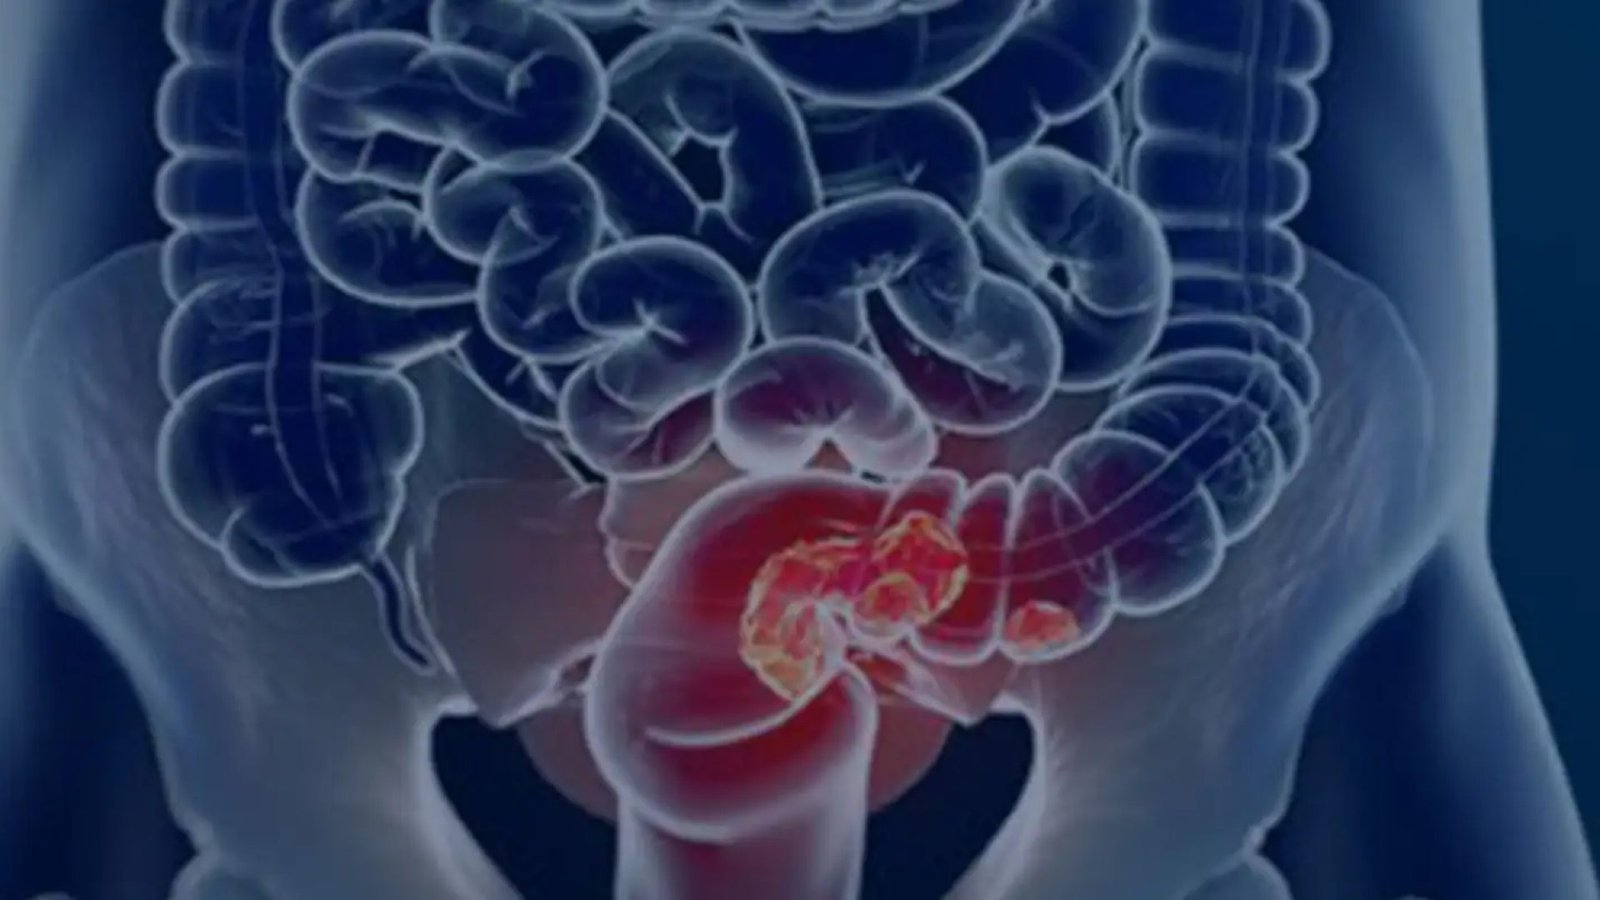

O câncer colorretal (CCR) apresenta um desafio significativo para a saúde pública no Brasil. Um estudo recente revelou que a maioria dos casos da doença é diagnosticada em estágios avançados, comprometendo as chances de cura. A detecção precoce, juntamente com a adoção de hábitos saudáveis, são cruciais para mudar esse cenário. A pesquisa enfatiza a necessidade urgente de estratégias de rastreamento mais eficazes e políticas públicas abrangentes para combater o avanço dessa doença no país. O aumento estimado de novos casos e óbitos até 2040 reforça a importância de ações imediatas e coordenadas.

Um estudo recente da Fundação do Câncer, divulgado durante o Dia Nacional de Combate ao Câncer, revelou dados alarmantes sobre o diagnóstico de câncer colorretal (CCR) no Brasil. Entre 2013 e 2022, dos 177 mil casos registrados em hospitais públicos e privados, mais de 60% foram diagnosticados em estágios avançados da doença. Essa demora no diagnóstico reduz significativamente as chances de cura e destaca a necessidade urgente de estratégias de detecção precoce e prevenção.

Impacto do Diagnóstico Tardio

A identificação do CCR em estágios avançados, como os estágios 3 e 4, é um fator crítico que afeta negativamente o prognóstico dos pacientes. O diretor-executivo da Fundação do Câncer, Luiz Augusto Maltoni, enfatizou que mais de 70% dos casos chegam ao sistema de saúde já em fases avançadas, o que representa uma situação catastrófica.

A detecção precoce do câncer colorretal é fundamental para aumentar as chances de cura e melhorar a qualidade de vida dos pacientes. Atualmente, o principal exame para rastreamento é a pesquisa de sangue oculto nas fezes, um método menos invasivo e de baixo custo. Quando o resultado é positivo, indica-se a colonoscopia para uma avaliação mais detalhada.